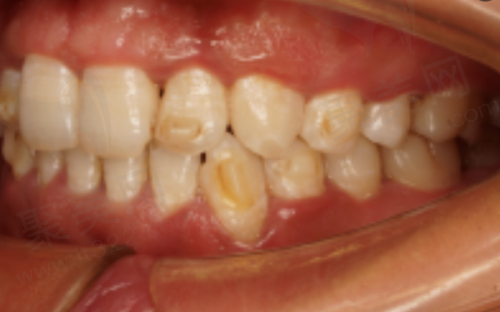

在追求健康和美丽的道路上,牙齿矫正成为了许多太原市民关注的项目。牙齿不仅关乎咀嚼功能,整齐美观的牙齿还能提升个人的形象和自信心。2025年,太原牙齿矫正市场呈现出多样化的态势,不同的矫正方式价格差异较大,而且国有和私立医院的收费也有所不同。接下来,我们就为大家详细揭秘2025年太原牙齿矫正的费用情况。

金属托槽矫正一直是牙齿矫正领域的经典方式。在2025年的太原,其价格范围在6800 - 15000元。这种矫正方式之所以受欢迎,是因为它的适用范围非常广泛。无论是牙齿拥挤、牙齿稀疏、龅牙还是地包天等常见的牙齿畸形问题,金属托槽矫正都能发挥良好的作用。

金属托槽矫正的原理是通过在牙齿表面粘贴金属托槽,然后利用钢丝的力量来移动牙齿,使其逐渐排列整齐。虽然金属托槽的外观可能不太美观,但是它的矫正成效是有目共睹的。而且,相对较低的价格让更多人能够接受这种矫正方式。像一些经济条件有限但又需要进行牙齿矫正的患者,金属托槽矫正就是一个不错的选择。